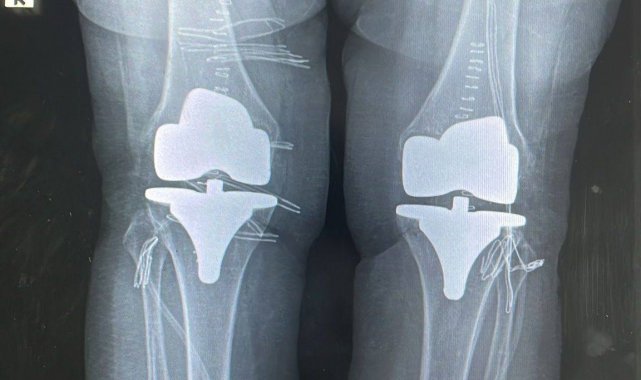

Bayburt Devlet Hastanesinde yapılan çift taraflı total diz protezi operasyonuyla 73 yaşındaki hastanın dizlerindeki ağrı giderildi. Başarılı geçen ameliyatla hasta sağlığına kavuştu.

Ortopedi polikliniğine dizlerindeki yoğun ağrı şikayetiyle başvuran 73 yaşındaki hastanın her iki dizinde ileri derecede kireçlenme tespit edildi. Ortopedi ve Travmatoloji Uzmanı Op. Dr. Reşat Arıkan tarafından gerçekleştirilen operasyonda, hastanın her iki dizine çift taraflı total diz protezi uygulandı. Tek seferde yapılan ve başarılı geçen bilateral ameliyatının ardından hastanın sağlık durumunun iyi olduğu öğrenildi.